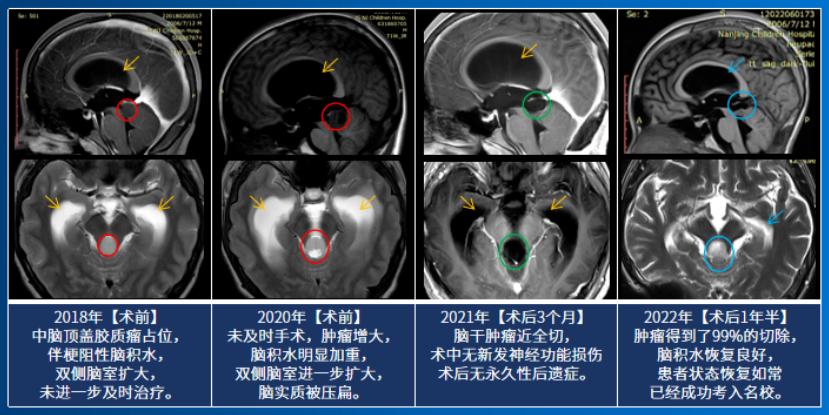

14岁的小永查出脑干胶质瘤,影像片子显示:脑干-中脑顶盖,伴有幕上脑室扩张积水,脑室及大脑实质已经受压变形。在与患者家属沟通中我们得知,小永2018年就出现过轻微头痛、头晕,去医院检查发现脑干肿瘤,并伴有梗阻性脑积水。小永的父亲咨询了很多知名专家。“每次都说毛细胞星形细胞瘤一般不长,观察就行,但是后来我最后一次去找他们的时候,我说症状太重,不行就做手术,他们最后和我说实话,因为做手术风险过大,所以说建议你观察……”这一拖就是2年多,孩子的病情越来越严重。

手术结果令人欣喜,小永的肿瘤得到近全切除,病理结果为毛细胞型星形细胞瘤,这是一种预后较好的胶质瘤,全切或近全切后复发率非常低。

去年7月,术后已经过了1年半,我们对小永进行随访时得知他已经凭借优秀的中考成绩,考入国家级示范高中,其中体育成绩还获得了满分,完全看不出来曾经做过开颅脑干手术。